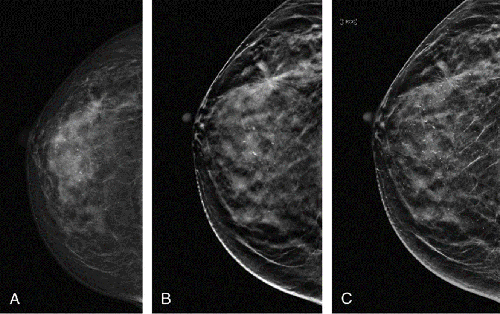

Breast Tomosynthesis

Breast tomosynthesis, also called three-dimensional (3-D) mammography and digital breast tomosynthesis (DBT), is an advanced form of breast imaging, or mammography, that uses a low-dose x-ray system and computer reconstructions to create three-dimensional images of the breasts. It reduces the rate of false positive readings (a reading that identifies normal tissue as an abnormality) and ensures that fewer women need to come back for another mammogram. It reduces the need for a biopsy and enables the healthcare provider to more accurately locate where the abnormality is in the breast.